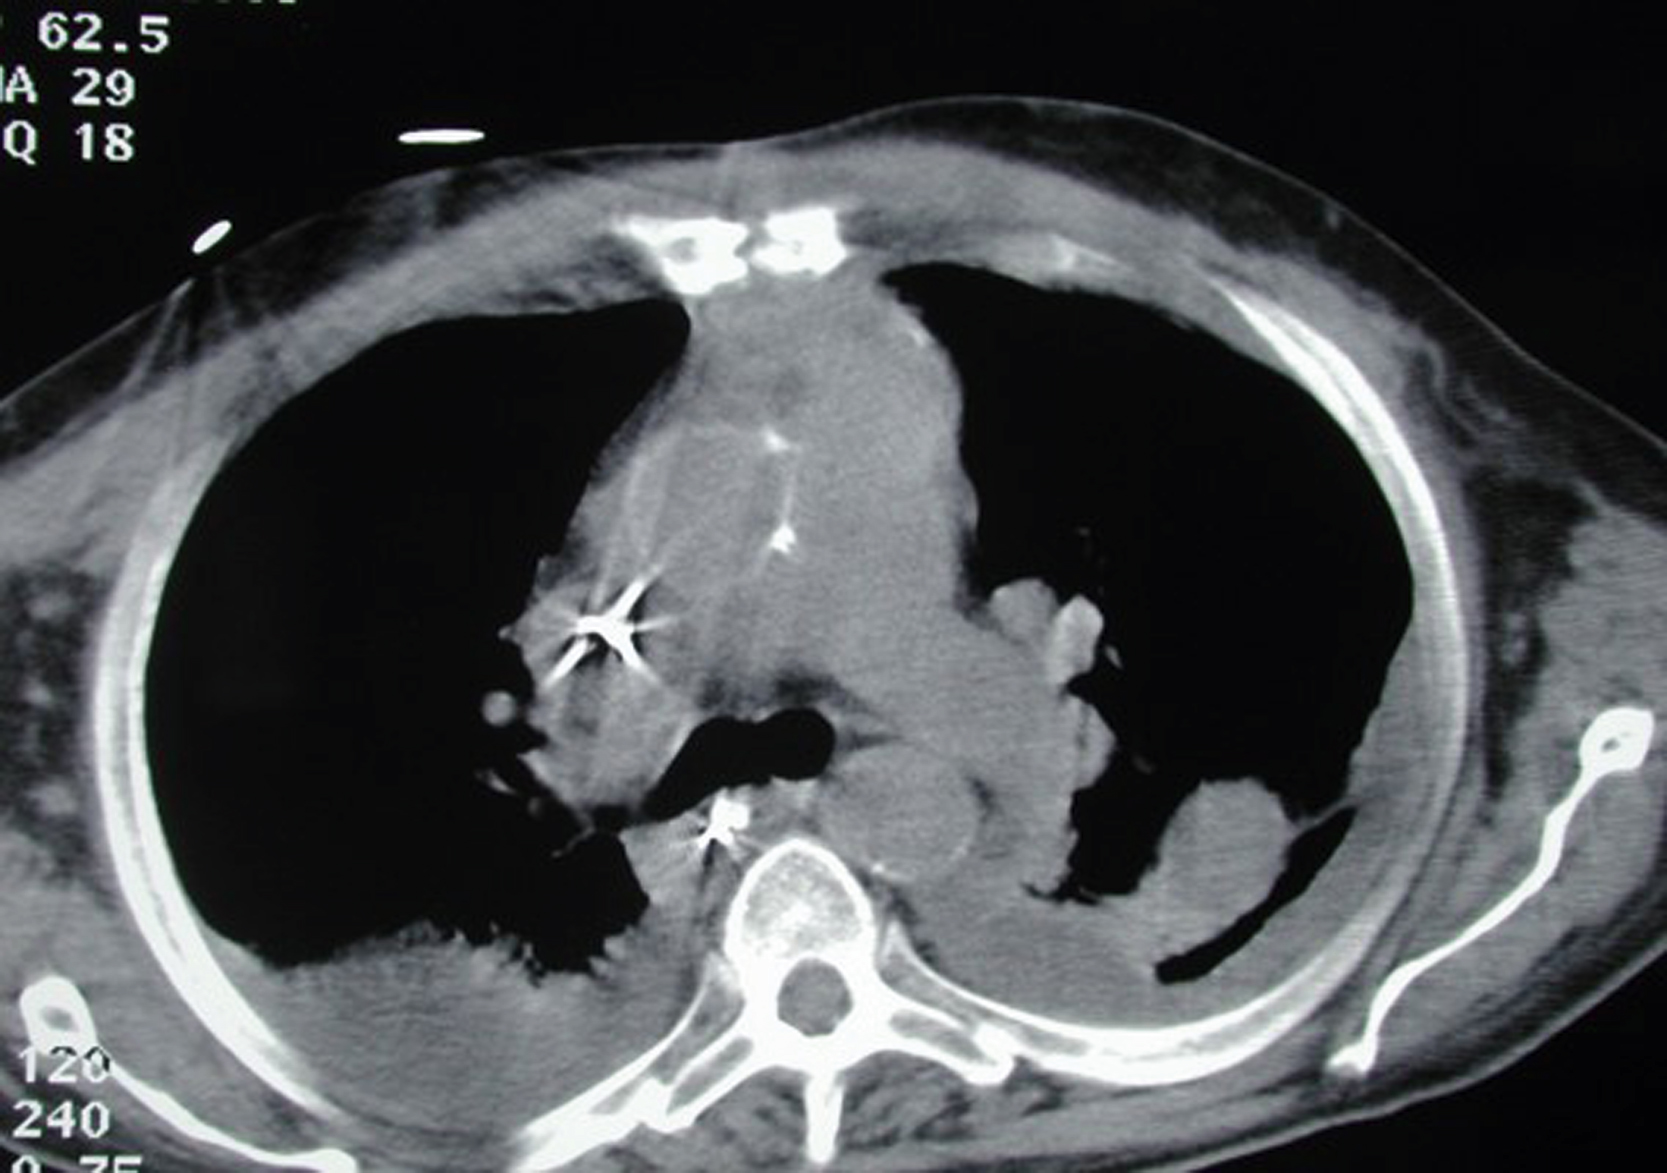

The patient was readmitted to the hospital 1 month later and a total gastrectomy with a Roux-en-Y esophageal jejunostomy and feeding jejunostomy was performed by the surgical oncology service. His postoperative course was complicated by prosthetic valve bacterial endocarditis, sepsis, and multisystem organ failure. He was also found to have a seroma under the intact closure of the upper sternal flap reconstruction ( Fig. 21.6 ). The sternal flap site was stable and there was no cellulitis. The etiology of this fluid collection was thought to be an infiltration after a central line placement. Approximately 100 cc of cloudy fluid was aspirated and a pressure dressing was applied to the sternal area. The final culture showed Candida albicans . Follow-up chest CT scans showed a healed sternal soft tissue closure with no substernal fluid collection ( Figs. 21.7 and 21.8 ).